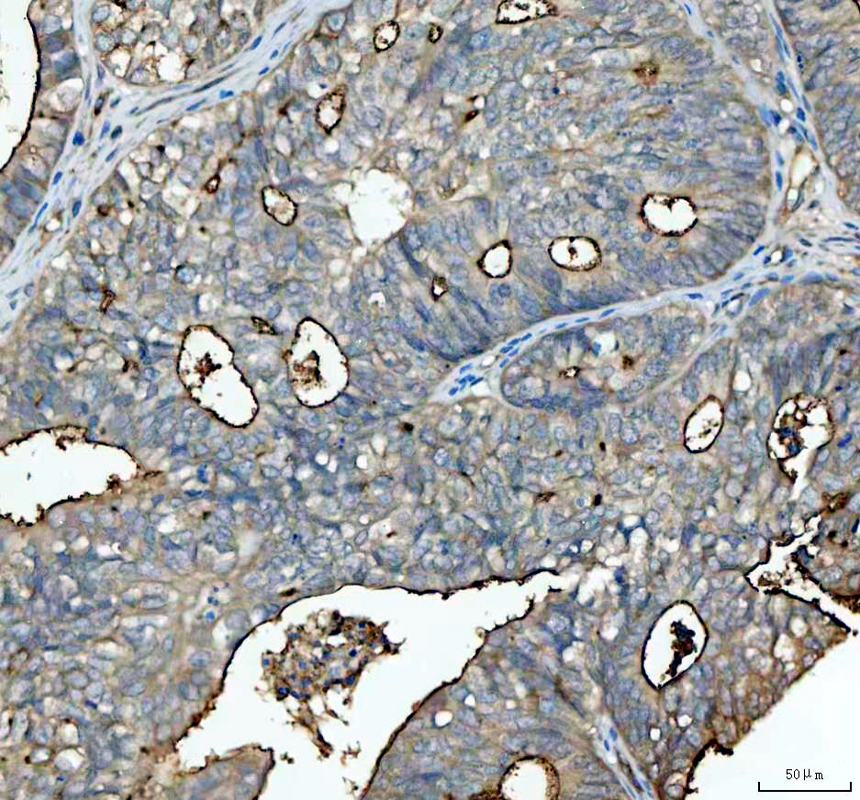

IHC analysis of CA15-3/MUC1 using anti-CA15-3/MUC1 antibody (A00187-2).

CA15-3/MUC1 was detected in a paraffin-embedded section of human endometrioid adenocarcinoma tissue. The tissue section was incubated with rabbit anti-CA15-3/MUC1 Antibody (A00187-2) at a dilution of 1:200 and developed using HRP Conjugated Rabbit IgG Super Vision Assay Kit (Catalog # SV0002) with DAB (Catalog # AR1027) as the chromogen.